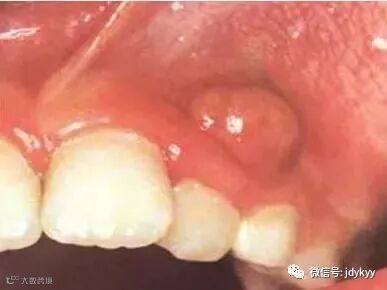

龋病可发展为牙髓炎、根尖周炎,引起剧烈疼痛,严重者还可造成间隙感染

图为根尖周炎导致的脓肿